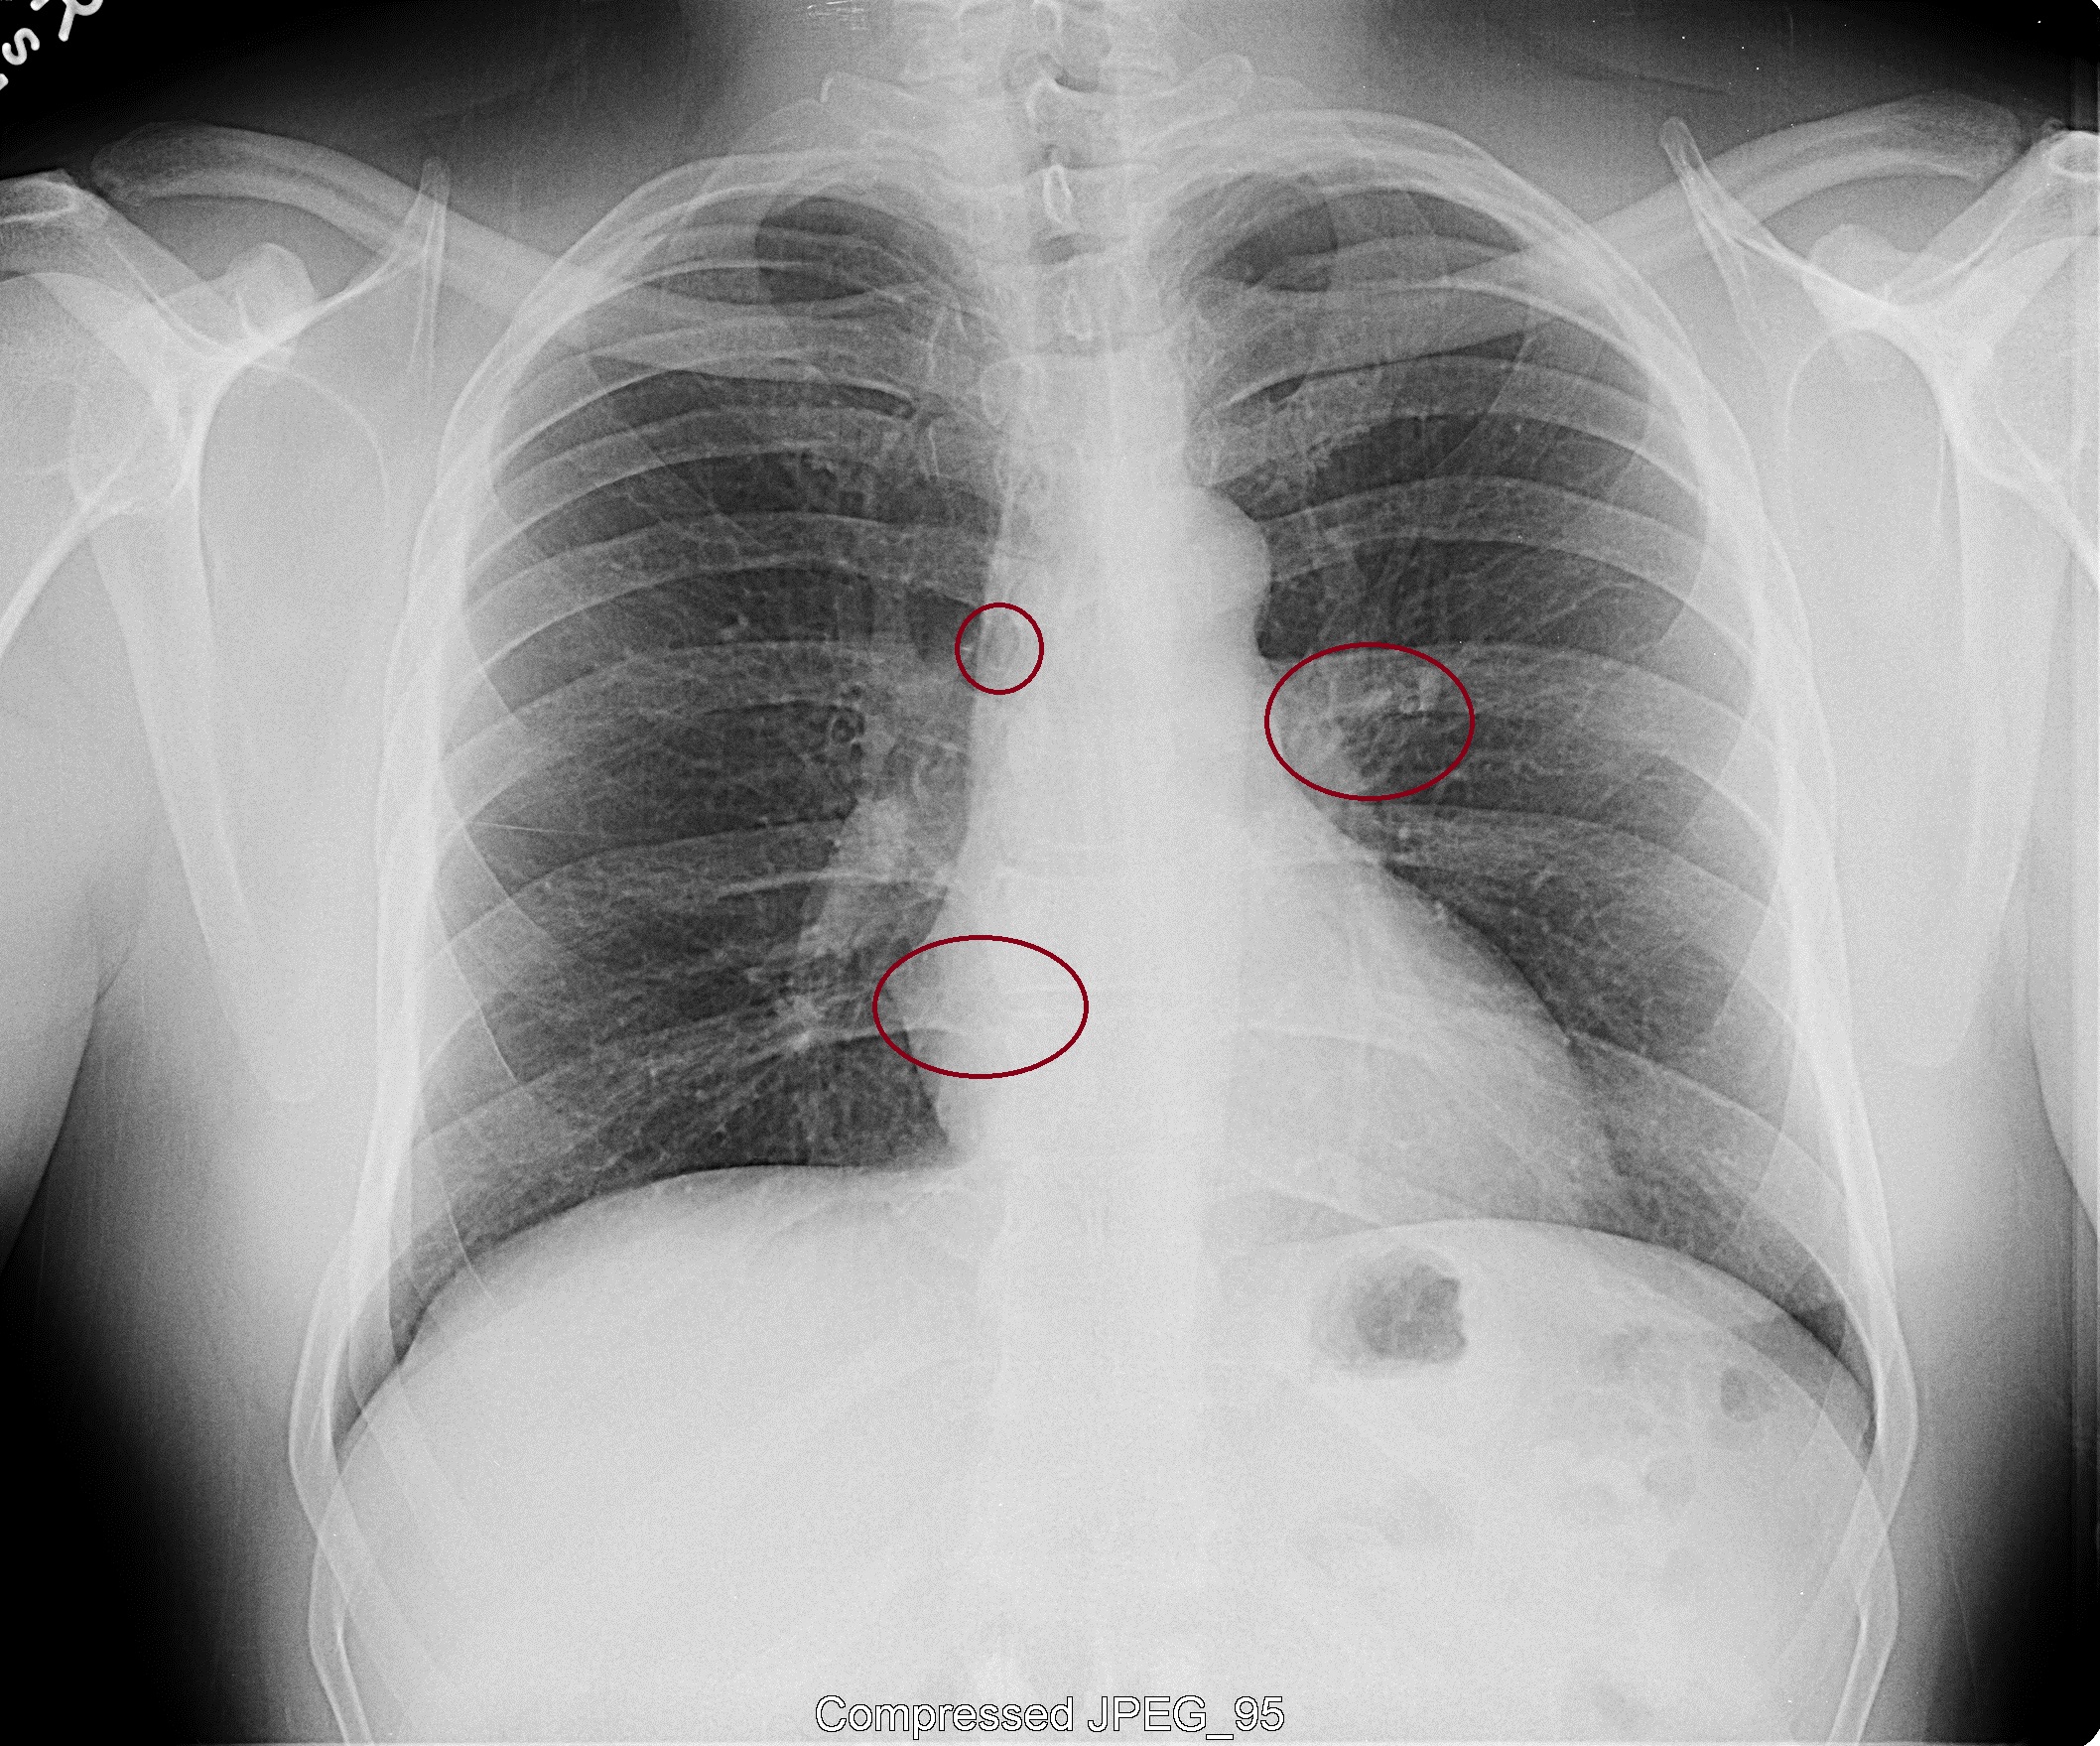

R. Cain Pueblo Radiology Chest Xray March 2, 2012If you’ve listened to my recent interview with Richard Cain explaining how  him and his two sons were illegally implanted with materials and constantly being harassed and tortured, then you know he is fighting this legally.